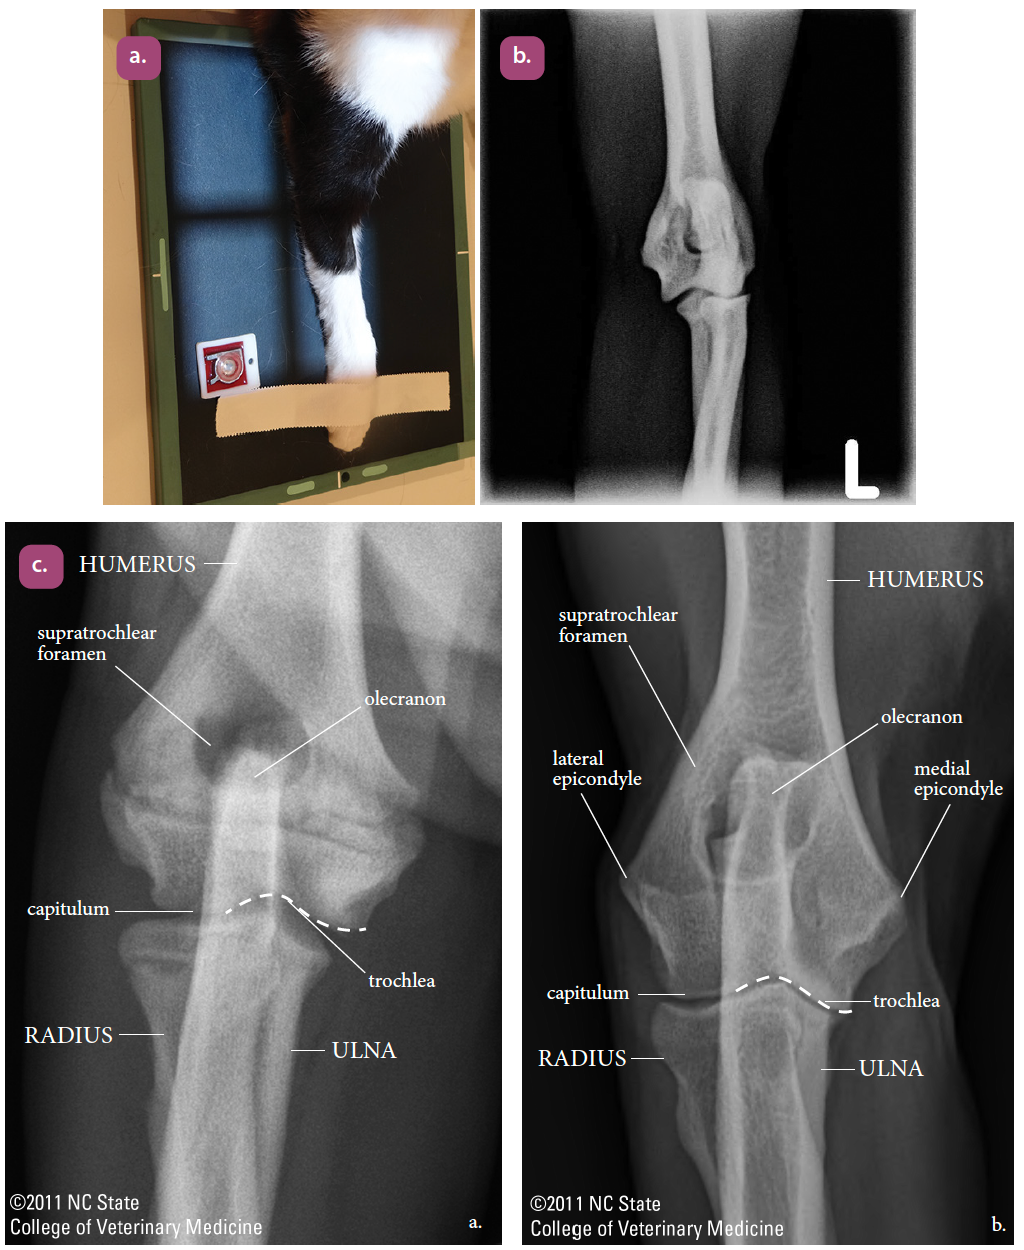

mediolateral projection of the elbow

craniocaudal projection of the elbow

flexed mediolateral projection of the elbow